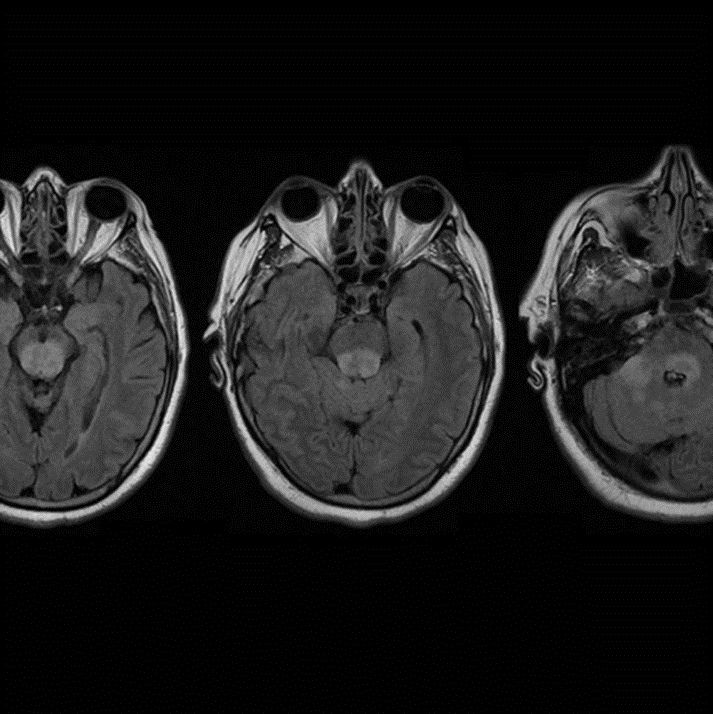

2. Deli meat / Listeria (rhomboencephalitis)